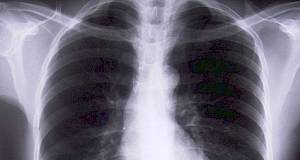

Pasivno pušenje aktivira složenu upalu u plućima

Otkrića će pomoći razvoju novih tretmana za respiratorne bolesti kod ljudi, otkriva nam istraživanje na štakorima. Jer izgleda da pasivno pušenje aktivira složenu upalu u plućima.

Dva mjeseca izloženosti pasivnom dimu je dovoljno da uzrokuje značajne promjene u plućima štakora, a te promjene se još više ističu nakon četiri mjeseca.